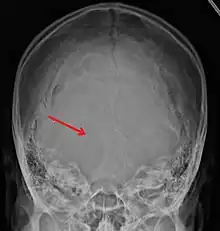

Linear

Linear skull fractures are breaks in the bone that transverse the full thickness of the skull from the outer to inner table. They are usually fairly straight with no bone displacement. The common cause of injury is blunt force trauma where the impact energy transferred over a wide area of the skull.

Linear skull fractures are usually of little clinical significance unless they parallel in close proximity or transverse a suture, or they involve a venous sinus groove or vascular channel. The resulting complications may include suture diastasis, venous sinus thrombosis, and epidural hematoma. In young children, although rare, the possibility exists of developing a growing skull fracture especially if the fracture occurs in the parietal bone.[2]